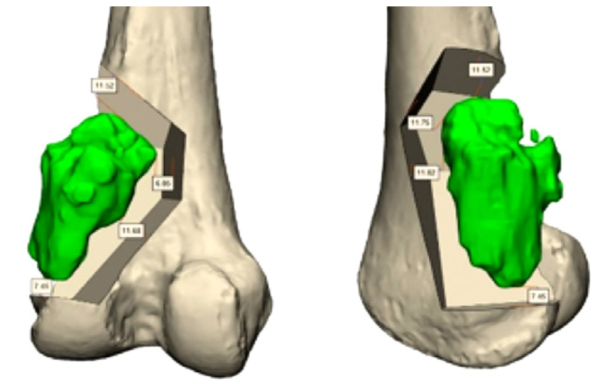

חידוש נוסף הוא השימוש במשתלים המותאמים אישית למטופל. לעיתים לא ניתן לשחזר את חסר העצם שנותר אחרי הכריתה בעזרת משתל רגיל, לדוגמה כאשר המחלה מערבת את עצמות האגן, חוליות עמוד השדרה או כשמדובר במטופלים צעירים מאוד עם ממדי גוף קטנים במיוחד. במקרים אלה לא הייתה בעבר יכולת לבצע שחזור כלשהו, ולכן פעמים רבות המטופלים נותרו עם מגבלה תפקודית קשה. ניתן לייצר משתל המותאם אישית למצב הקליני הייחודי של המטופל, לעיתים בשיטות ייצור מסורתיות, ולעיתים בהדפסה תלת-ממדית.

חידוש חשוב שבא לידי ביטוי בניתוחים לטיפול בממאירויות עצם ראשוניות, הוא בשיטות לניווט תוך ניתוחי. באופן מסורתי, המנתח מעריך את מיקום החיתוך הנדרש, כדי לכרות את הגידול עם שולי כריתה בטוחים מבחינת אונקולוגית, מבלי להקריב רקמה בריאה מעבר לנדרש, כדי לא לגרום לפגיעה תפקודית מיותרת. קיים הבדל גדול בין מנתחים שונים ביכולתם להעריך את מיקום החיתוך בצורה מדויקת. ישנם כלי עזר שמסייעים למנתח במשימה זו, החל בבדיקות דימות תוך ניתוחיות, דוגמת CT תוך ניתוחי, עם הצגה של מיקומם בפועל של כלי הניתוח בהשוואה לתכנון הניתוחי, וכלה בתבניות חיתוך מותאמות אישית בהדפסה תלת-ממדית, אשר מכוונות את כלי הניתוח אל המסלול המתוכנן.